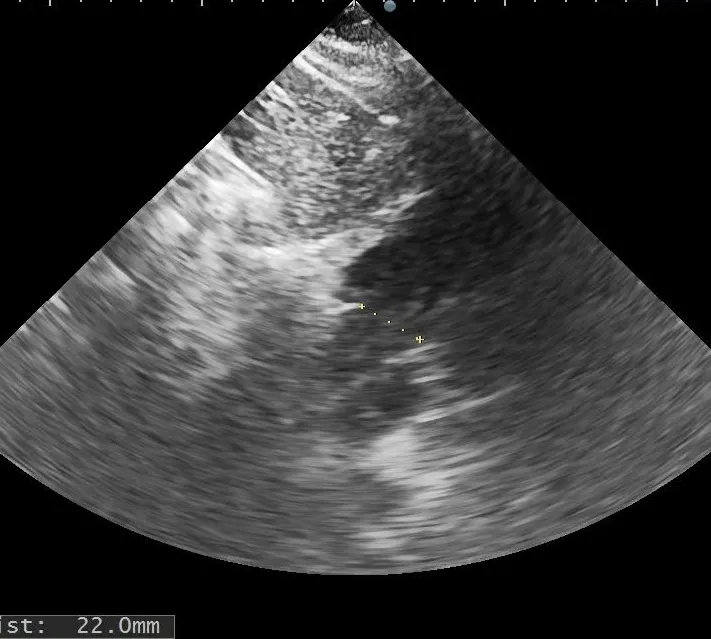

术前复测

多切面测量房间隔缺损直径为

20.5mm×22.0mm×21.6mm